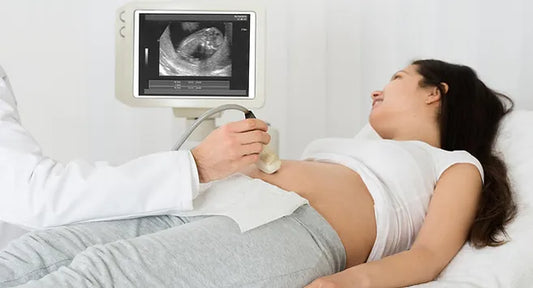

Ultrasound : Overview

What is an ultrasound scan? An ultrasound scan sends high-frequency sound waves through your uterus (womb). These sound waves bounce off your baby and the echoes are turned into an...